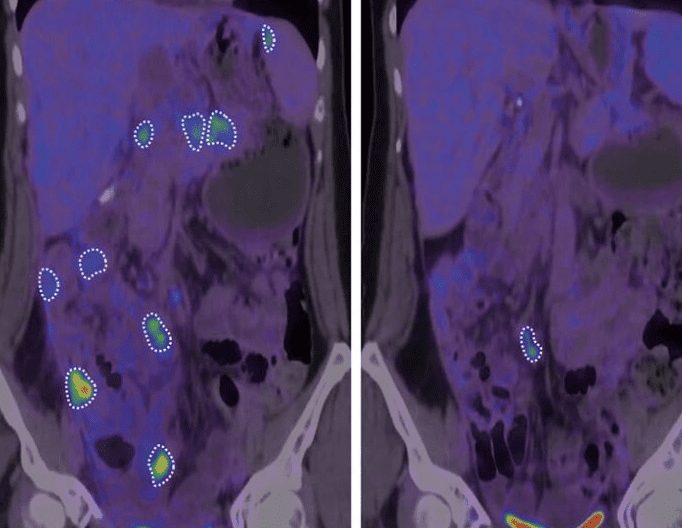

초기 실험에서 간암에 걸린 원숭이들을 대상으로 한 결과, 바이러스를 투여받은 원숭이들은 치료 효과를 확인할 수 있었습니다. 특히, 인간 대상 임상 시험에서는 암세포의 성장이 멈추거나 크기가 줄어드는 사례가 발견되었습니다. 하지만 모든 환자가 동일한 치료 효과를 본 것은 아니며, 연구진은 추가 연구를 통해 이 방법을 최적화할 계획입니다.

이번 연구는 다양한 동물 실험과 초기 인체 임상 시험을 통해 신뢰성을 확보했어요. 연구진은 특정 바이러스가 암세포 표면의 당 구조를 변형시키도록 유도해 면역 체계가 이를 외부 세포로 인식하도록 만들었어요.

✅ 연구 진행 과정- 🧬 실험 대상: 간암에 걸린 원숭이 및 초기 인간 임상 참가자

- 💉 실험 방법: 면역 활성화 바이러스 주입 후 면역 반응 측정

- 📊 결과 확인: 암세포 성장 억제 및 크기 감소 효과